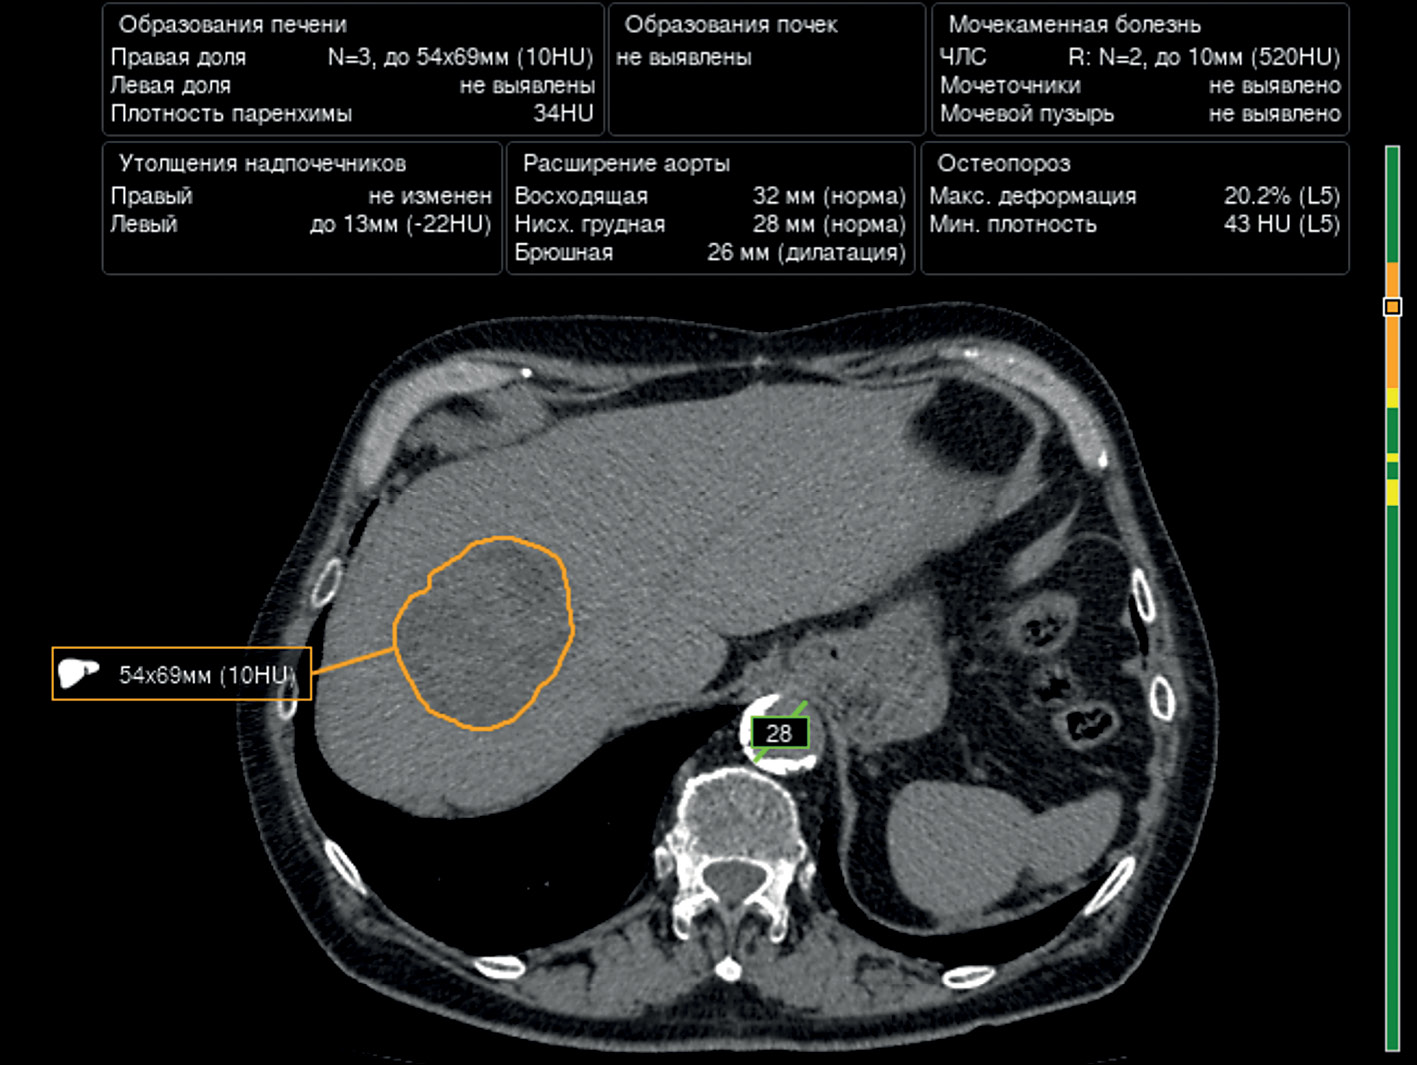

The article presents a selective literature review on the use of computer vision algorithms for the diagnosis of liver and kidney neoplasms and urinary stones using computed tomography images of the abdomen and retroperitoneal space. The review included articles published between January 1, 2020, and April 24, 2023. Pixel-based algorithms showed the greatest diagnostic accuracy parameters for segmenting the liver and its neoplasms (accuracy, 99.6%; Dice similarity coefficient, 0.99). Voxel-based algorithms were superior at classifying liver neoplasms (accuracy, 82.5%). Pixel- and voxel-based algorithms fared equally well in segmenting kidneys and their neoplasms, as well as classifying kidney tumors (accuracy, 99.3%; Dice similarity coefficient, 0.97). Computer vision algorithms can detect urinary stones measuring 3 mm or larger with a high degree of accuracy of up to 93.0%. Thus, existing computer vision algorithms not only effectively detect liver and kidney neoplasms and urinary stones but also accurately determine their quantitative and qualitative characteristics. Evaluating voxel data improves the accuracy of neoplasm type determination since the algorithm analyzes the neoplasm in three dimensions rather than only the plane of one slice.